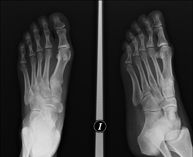

- Bone age X-ray

X-ray examination of the hand to assess the patient’s age based on the development of the bones and to determine if there is a delay or growth greater than that corresponding to the patient’s age.